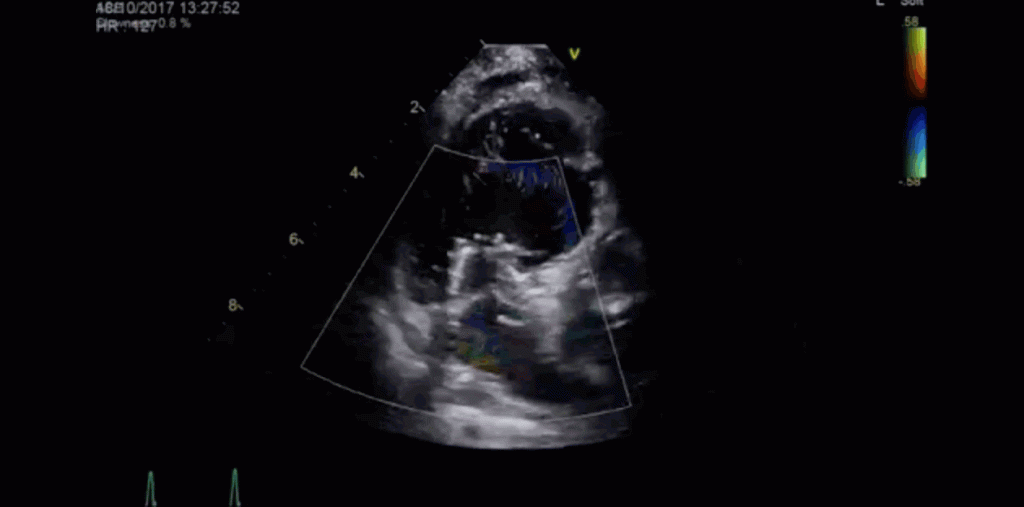

Other ultrasound systems can visualize blood flow as it moves through the hearts of the tiniest patients, down to the blood cells. Other devices, like the Vscan Extend, which fits into a physician’s pocket, help doctors diagnose and treat patients in remote areas far from medical centers.

width= Software from GE Healthcare enabled Dr. Ferran Rosés i Noguer and his team to enhance ultrasound images and track blood cells as they traveled through the heart. GIF credits: Dr. Ferran Rosés i Noguer.